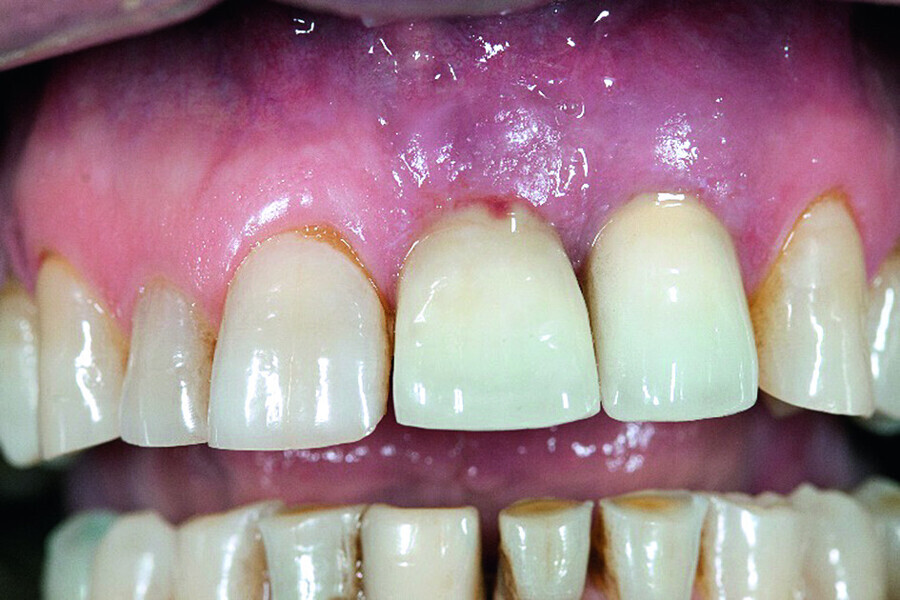

Peri-implantitis therapy